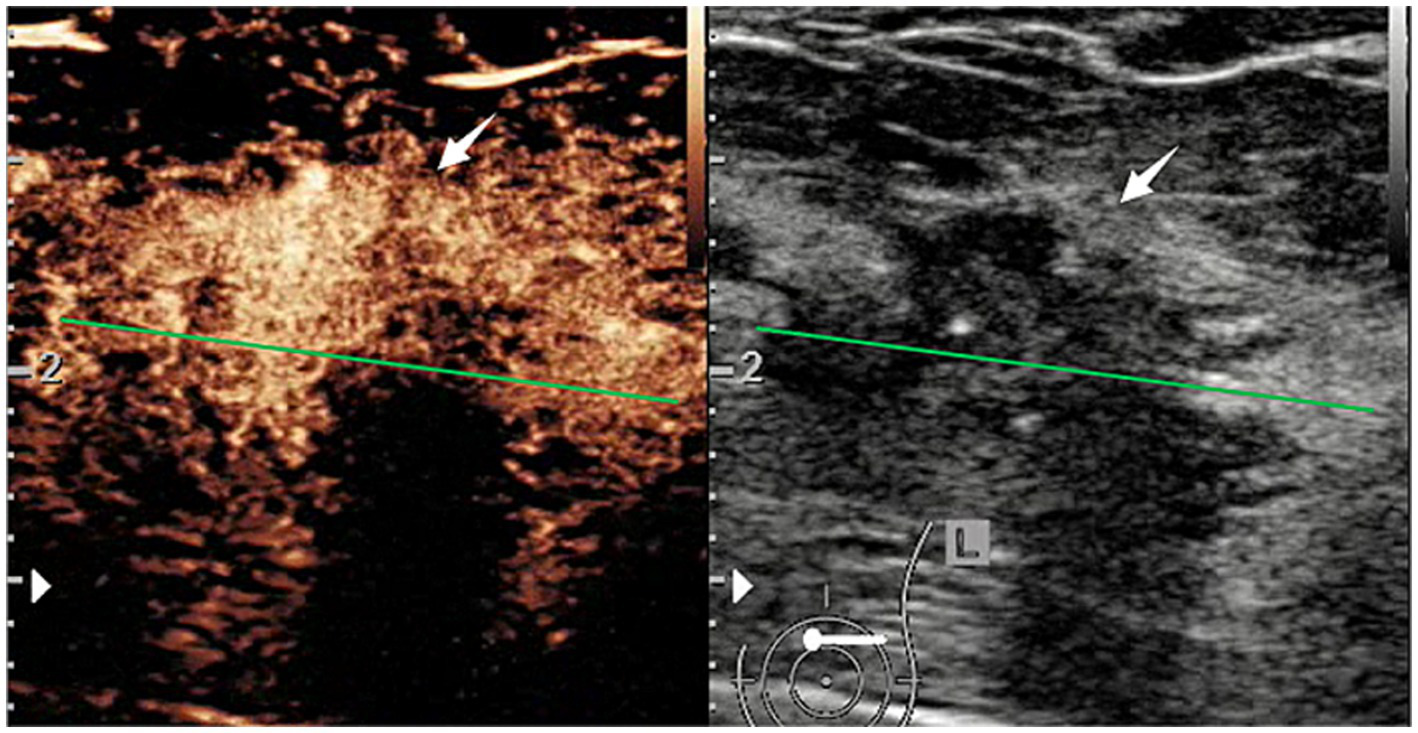

Figure 2

CEUS and B-mode ultrasound images of a patient with HER2-positive breast cancer.

In B-mode breast ultrasound, the “strip-shaped echoic” feature represents thin, elongated, and hyperechoic lines or bands within the breast tissue or mass. CEUS characteristics were evaluated, including shape (regular or not), margin (well or poorly defined), wash-in time (earlier, later, synchronous), enhancement degree (hyperenhancement, isoenhancement, hypoenhancement), complete wash-out time of lesions (≤5 min or not), uptake pattern (centripetal, centrifugal, diffuse, no enhancement), as well as exhibitions of the homogeneous pattern, rim-like enhancement, claw-shaped pattern, perfusion defects, lesion size compared with conventional ultrasound increased, and nourishing vessels. The time-intensity curve (TIC) features were evaluated using external perfusion software (VueBox™) to quantitatively evaluate the microvasculature of the tumors through the CEUS videos.